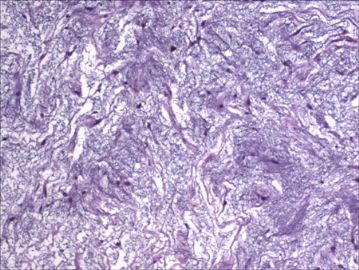

大腿肿物

肌内粘液瘤